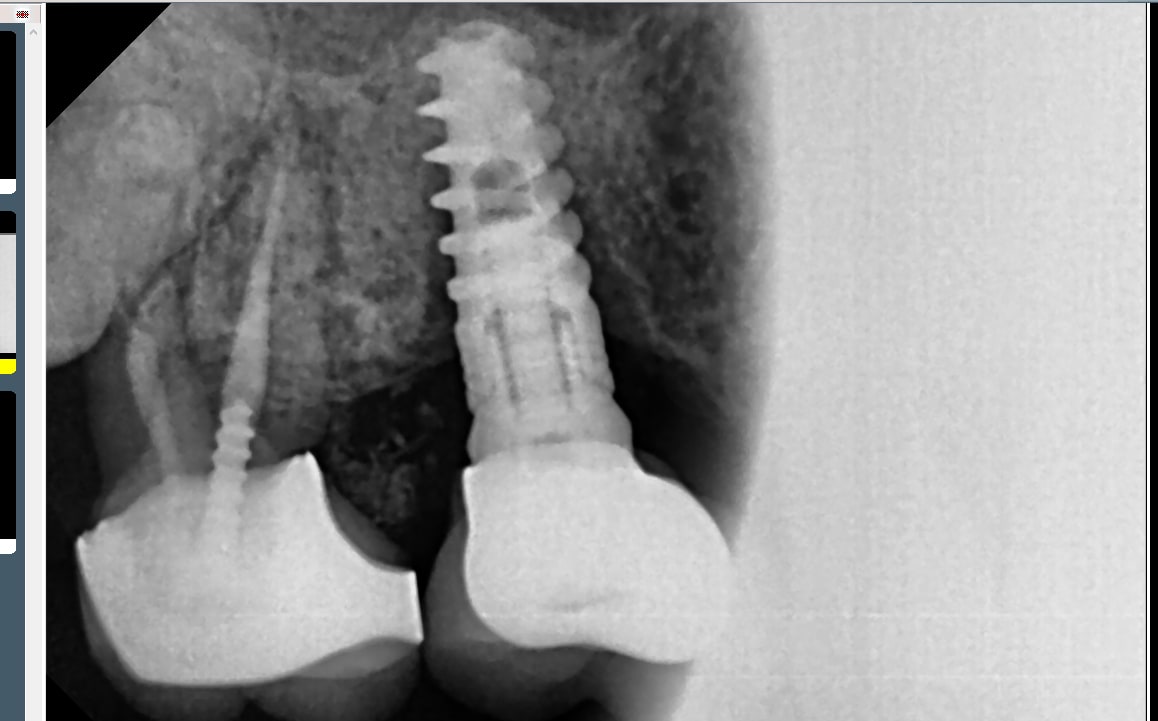

Je cherche à identifier cet implant posé en France il y a 10-15 ans, praticien en retraite.

Axiom reg Anthogyr

Alphabio

https://alphabiofrance.com/fr/co-interne-hexagonale-ih/2-spiral-implant.html